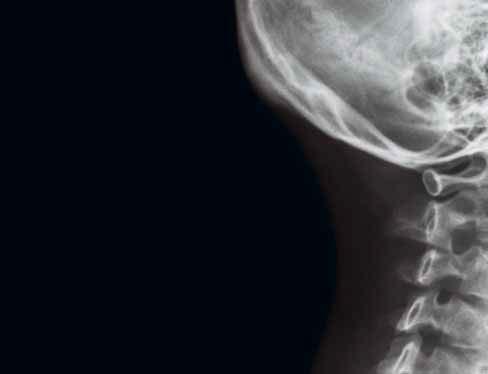

1 lamina externa

2 diploe

3 lamina interna

4 sutura coronalis (šev korunový)

5 sulcus arteriae meningeae mediae

6 sinus frontalis (dutina kosti čelní)

7 fossa hypophysialis (jamka tureckého sedla pro hypofýzu)

8 ala major ossis sphenoidalis (velké křídlo kosti klínové)

9 sutura lambdoidea (šev lambdový)

10 lamina cribrosa

11 processus clinoideus anterior (přední kuželovitý výběžek)

12 processus clinoideus posterior (zadní kuželovitý výběžek)

13 os nasale (kost nosní)

14 sinus sphenoidalis (dutina kosti klínové)

15 os zygomaticum (kost lícní, laterální stěna orbity/očnice)

16 clivus

17 cellulae ethmoidales (etmoidální sklípky, dutinky kosti čichové)

18 pars petrosa ossis temporalis (pyramida / kost skalní kosti spánkové)

19 sinus maxillaris (dutina horní čelisti)

20 porus acusticus externus (otvor zevního zvukovodu)

21 processus coronoideus mandibulae (krkavčitý výběžek dolní čelisti)

22 foramen magnum

23 processus zygomaticus (lícní výběžek)

24 palatum durum (tvrdé patro)

25 nasopharynx (nosohltan)

26 palatum molle (měkké patro)

27 mandibula (dolní čelist)